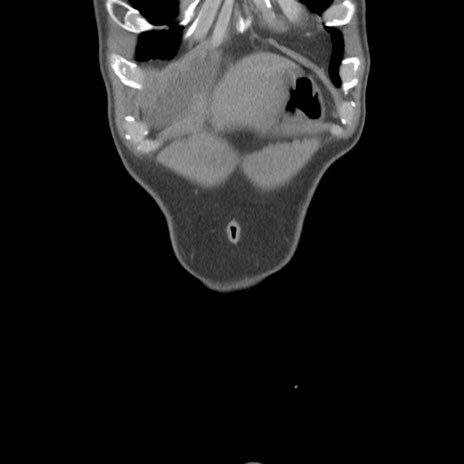

症例56 CT(冠状断像)

横断像